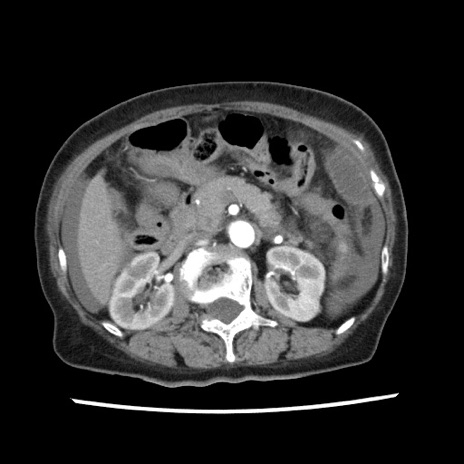

冠状断像

【症例】80歳代女性

【主訴】腹痛

【現病歴】8時間前から腹痛あり来院。

【既往歴】糖尿病、脂質異常症、子宮体癌にて子宮全摘術

【身体所見】意識清明・会話良好だが腹痛で苦悶様、全腹部にわたって反跳痛と圧痛あり

【データ】WBC 13600、CRP 0.14、LDH 224、CK 90